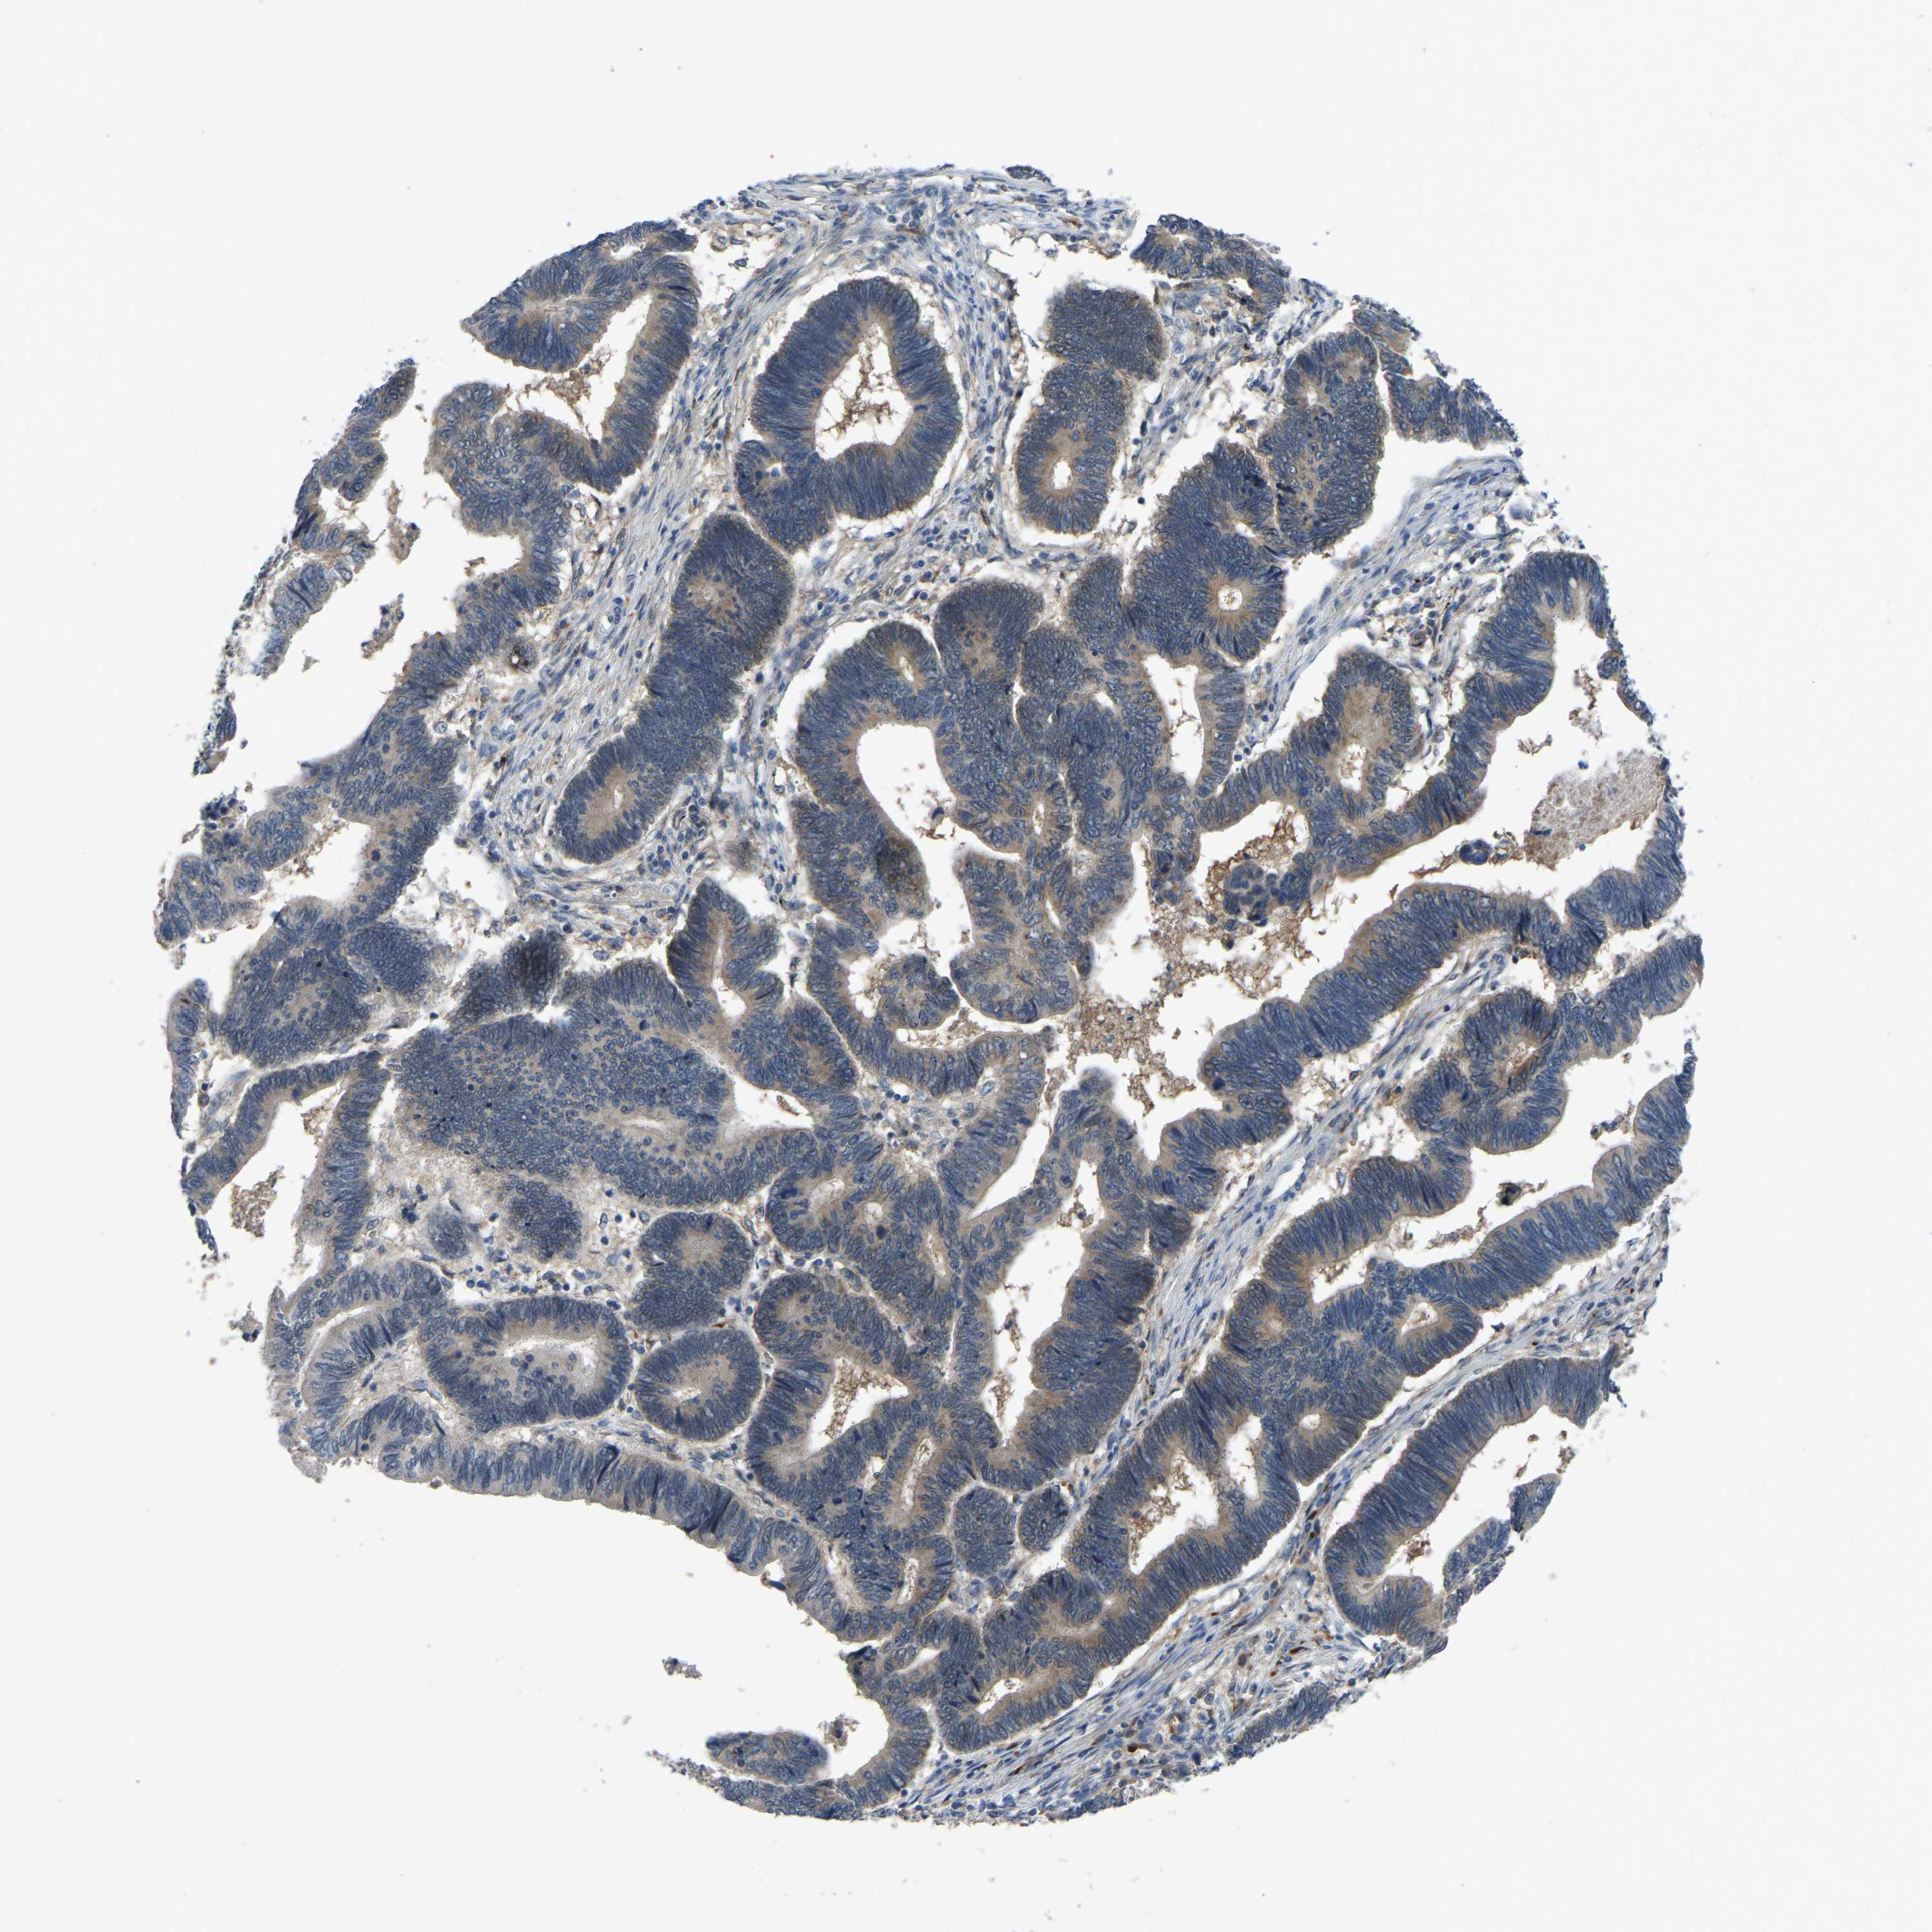

PANCREATIC CANCER - Protein expressioni

A mouse-over function shows sample information and annotation data. Click on an image to view it in a full screen mode. Samples can be filtered based on level of antibody staining by selecting one or several of the following categories: high, medium, low and not detected. The assay and annotation is described here.

Note that samples used for immunohistochemistry by the Human Protein Atlas do not correspond to samples in the TCGA dataset.

Antibody stainingi

Antibody staining in the annotated cell types in the current human tissue is reported as not detected, low, medium, or high, based on conventional immunohistochemistry profiling in selected tissues. This score is based on the combination of the staining intensity and fraction of stained cells.

Each image is clickable and will lead to virtual microscopy that enables deeper exploration of all samples and also displays staining intensity scores, fraction scores and subcellular localization as well as patient and tissue information for each sample.

Antibody HPA018840

Antibody HPA018909

Antibody CAB002684

Staining

High

Medium

Low

Not detected

Intensity

Strong

Moderate

Weak

Negative

Quantity

>75%

75%-25%

<25%

None

Location

Nuclear

Cytoplasmic/membranous

Cytoplasmic/membranous,nuclear

Adenocarcinoma, NOS

Adenocarcinoma, metastatic, NOS